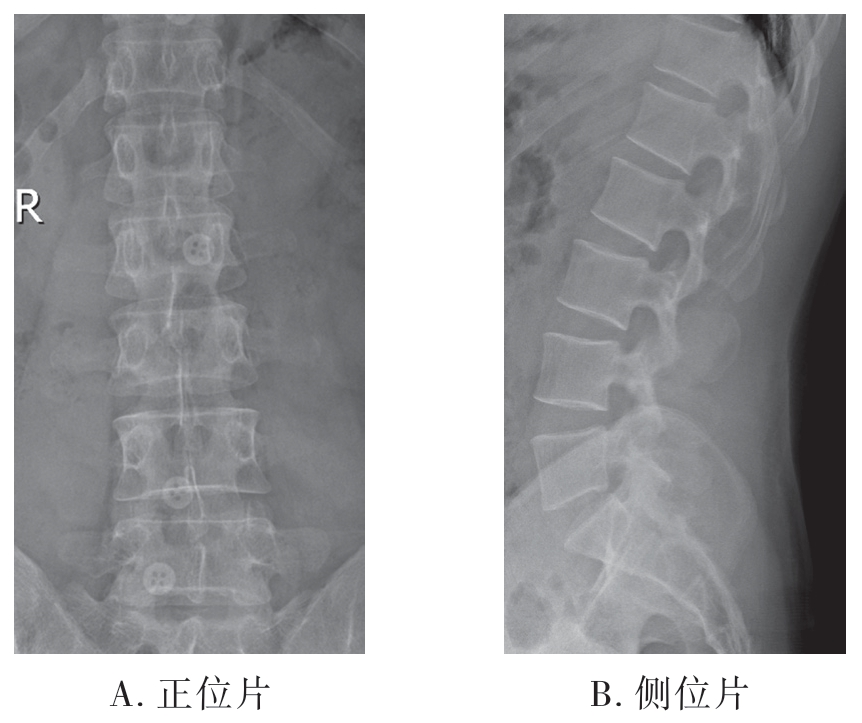

1)正位X线片:可显示腰椎的椎体、椎间隙、小关节、棘突、横突、骶髂关节、骶椎及周围软组织(图7-2-4A)。

2)侧位X线片:可显示腰椎椎体、椎间隙、小关节、棘突、椎间孔及周围软组织(图7-2-4B)。

图7-2-4 腰椎X线片